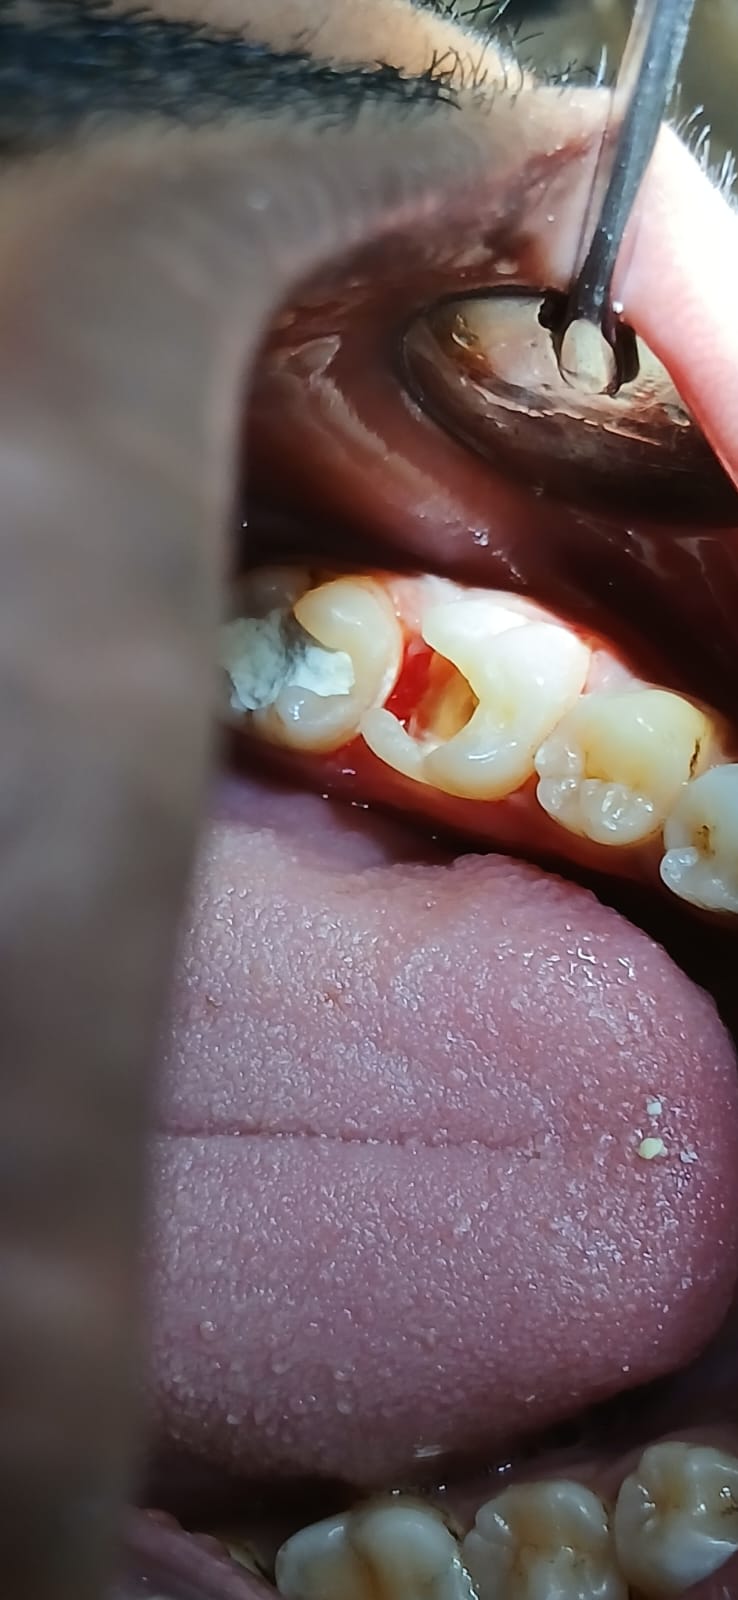

আগে ও পরে

আমাদের সফল কম্পোজিট রেস্টোরেশনের কিছু উদাহরণ

সামনের দাঁতের ক্ষয় মেরামত

ভাঙা দাঁত পুনর্গঠন

দাঁতের ফাঁক বন্ধ

ছবিতে ক্লিক করে বড় করে দেখুন। আরও কেস স্টাডি দেখতে ক্লিনিকে আসুন।